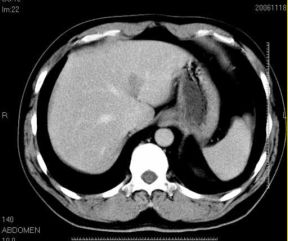

男性,48岁

肝内占位,性质?

肝内多发低密度占位病变,边缘清晰,无强化,肝转移瘤可能

肝内多发低密度占位病变,边缘清晰,无强化,肝转移瘤可能大,请将胃喝水充盈以后再扫描看看,我看大弯侧胃壁较厚。

肝内多发不规则形状低密度灶,强化不明显,考虑转移,积极查找原发灶

肝内多发低密度类圆形病灶,边缘清晰.增强无强化.

意见:1,考虑多发转移瘤;

2,囊肿与血管瘤不排除.

1肝内多发低密度影,考虑:转移瘤 2胃大弯侧胃壁明显增厚,建议胃镜检查除外胃癌